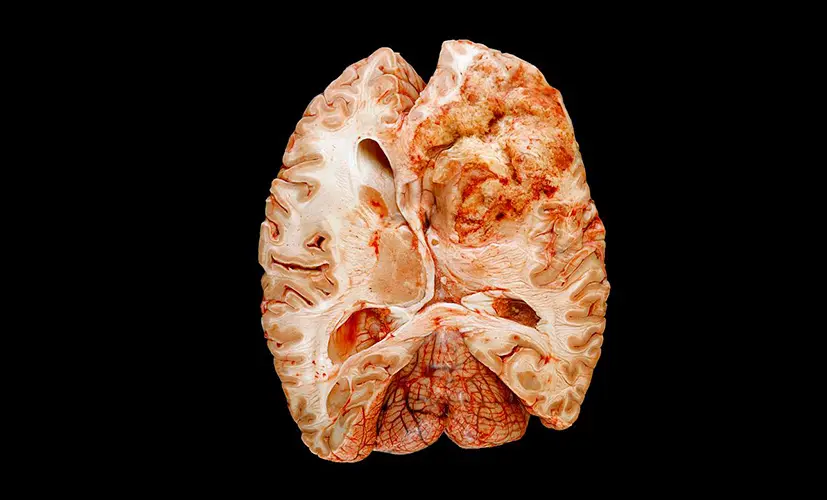

1.Complete memory loss - a life without clarity

The neural pathways in the brain become so damaged that no supplement can help. The person permanently loses their ability to recall memories. Relationships deteriorate. Confidence shatters. Depression takes hold. I've seen patients who isolated themselves at home, unable to face their loved ones.

2. Dementia - the silent thief

Untreated cognitive decline can evolve into dementia. It may start as occasional forgetfulness, but before you know it, the condition has spread, impairing judgment and daily function. Patients describe the mental haze as a fog they can't escape. Most are diagnosed too late-when little more can be done.

5. Nerve damage and mental confusion

Chronic cognitive decline can destroy the nerves responsible for mental processing and focus. Suddenly, you lose control over your thoughts. Mental disarray becomes your daily reality-even at a young age. People tell me they're too ashamed to engage with others. This isn't an "old person's condition"-it can happen to anyone.